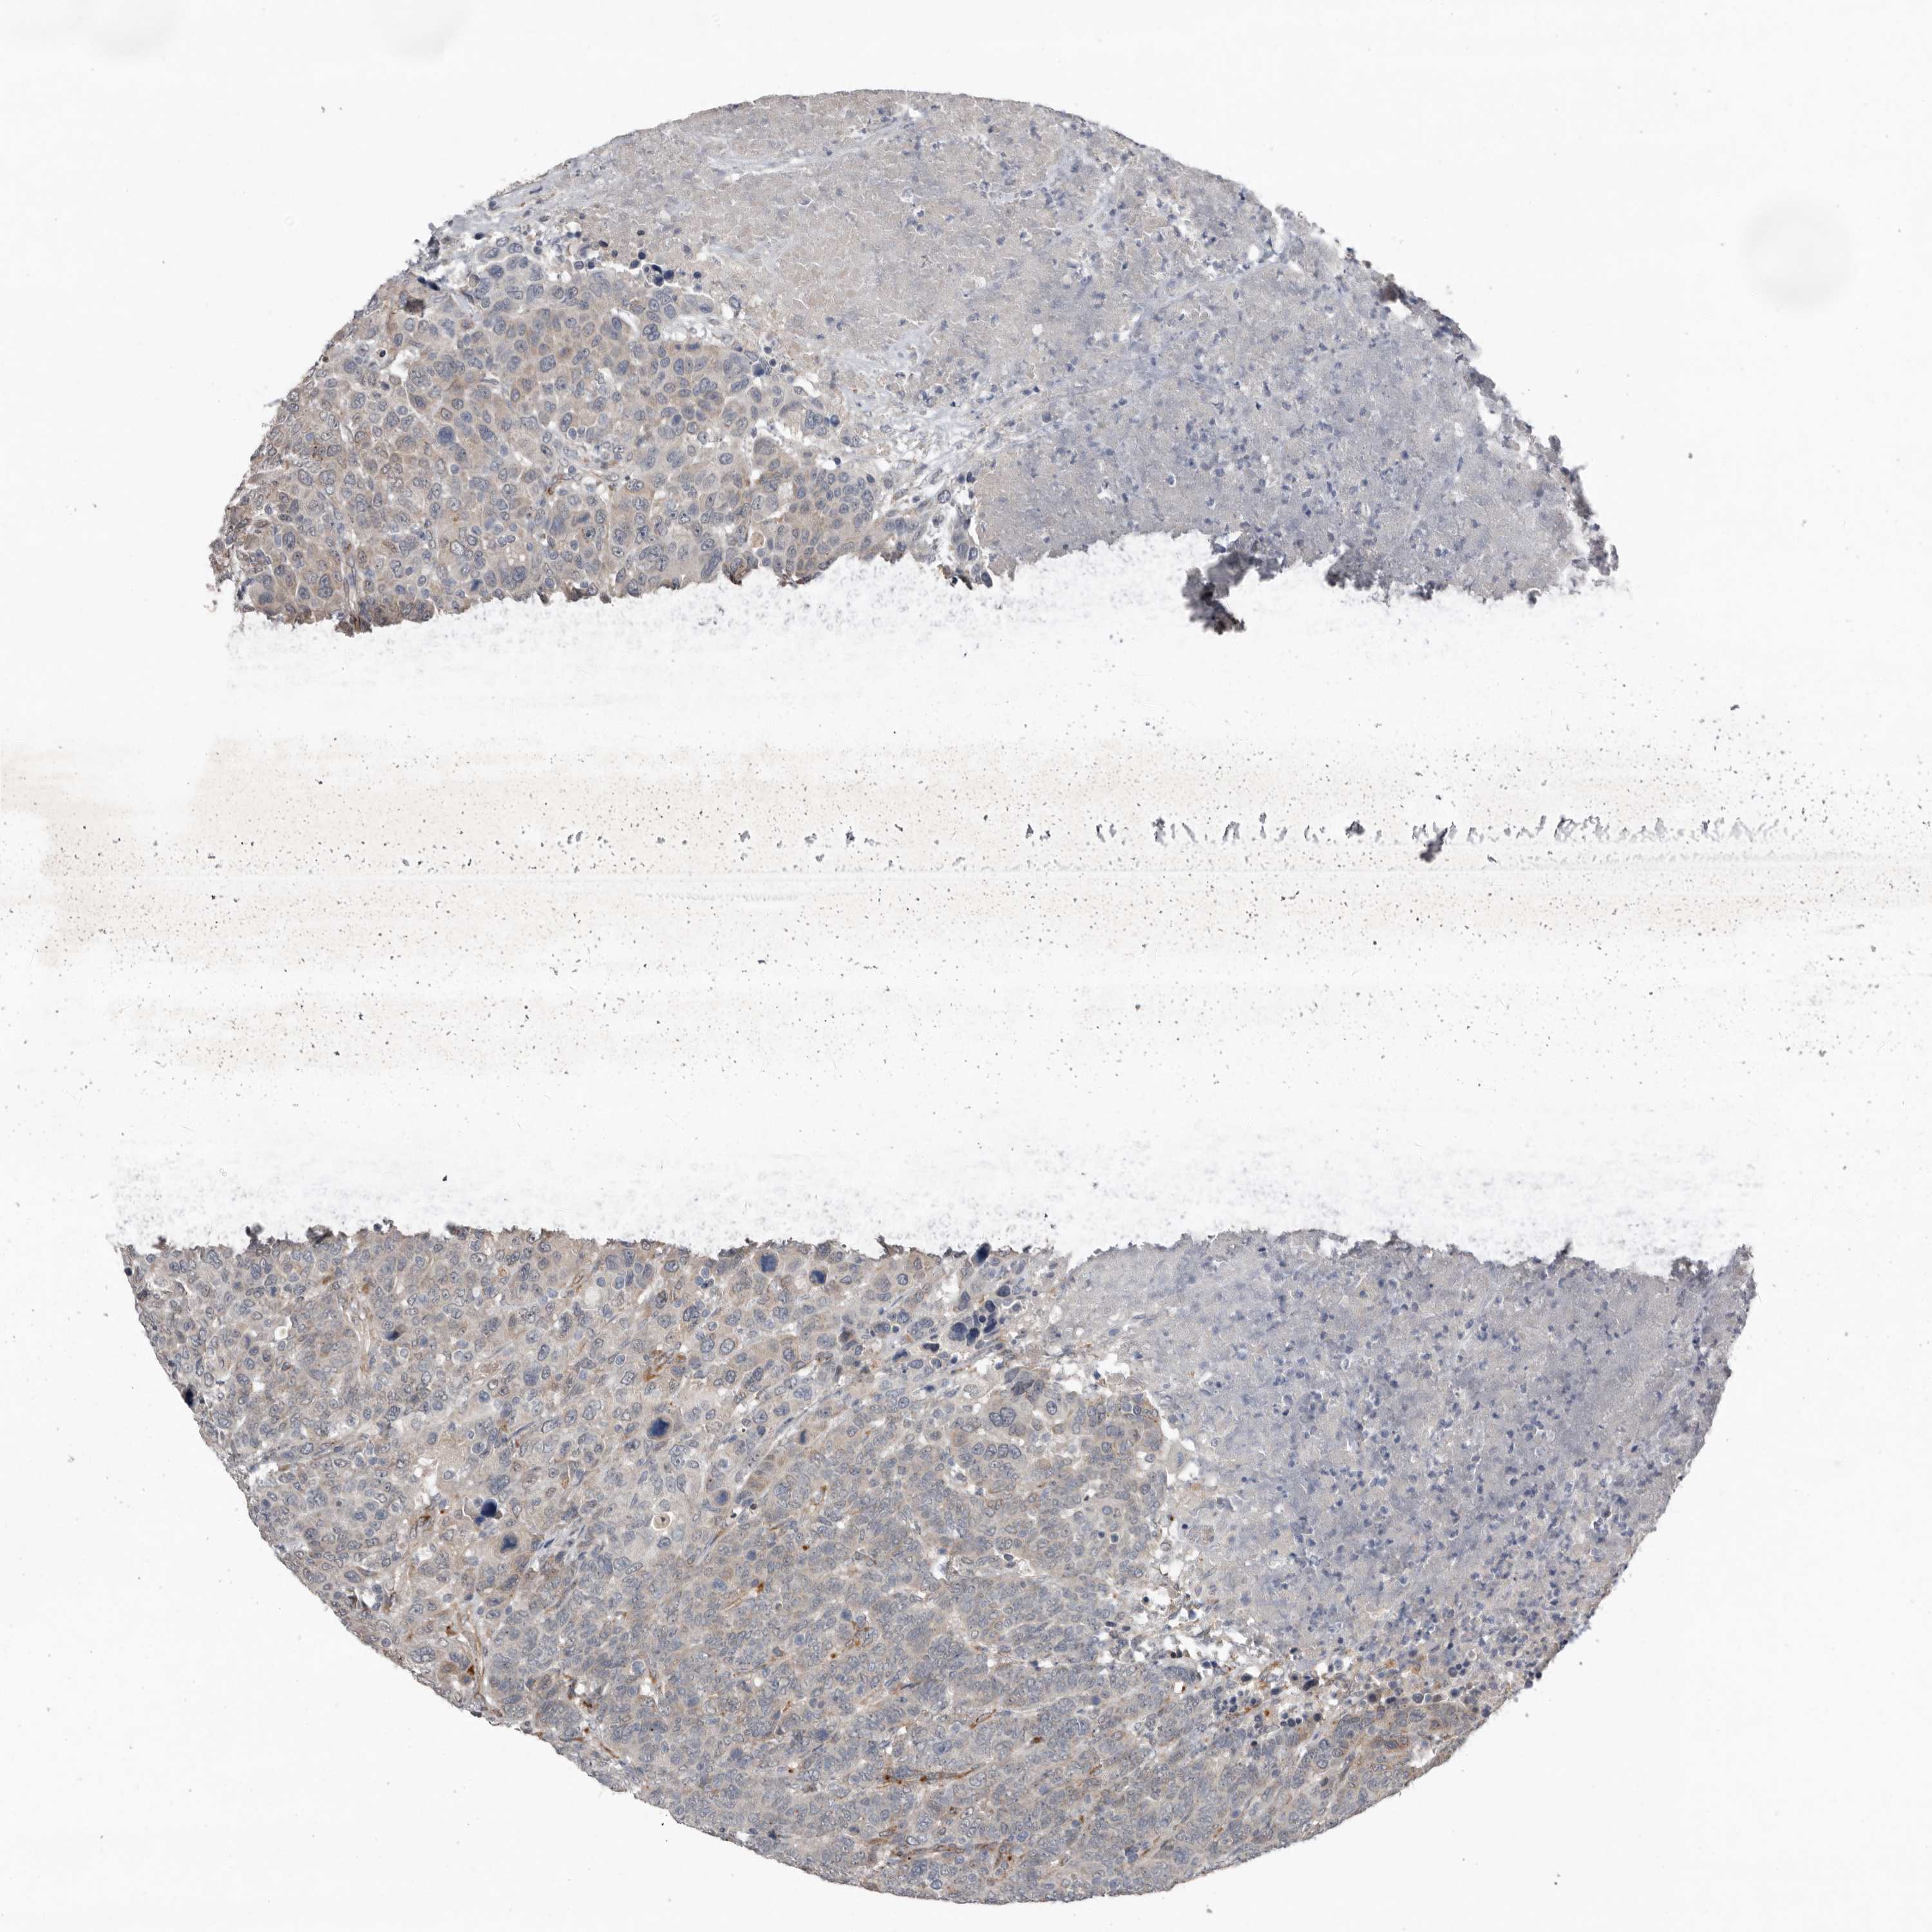

CANCER BREAST CANCER Show tissue menu

BRCA TCGA BRCA VALIDATION PROTEIN EXPRESSION

ANTIBODIES

AND

VALIDATION